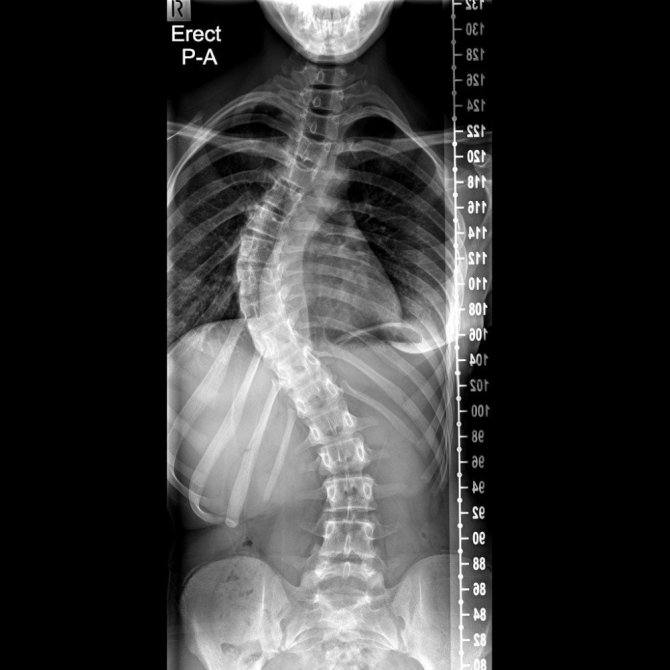

Başın bir tarafa doğru eğimli olması, göğüs kafesinde asimetri, kürek kemiklerinden birinin diğerine göre daha tümsek şeklinde olması, kalçalar ve omuz seviyeleri eşit olmaması, bacak eşitliklerinin aynı olmadığından şikayet edilmesi gibi durumlar skolyoz habercisi olabileceğinin beliren Prof. Dr. Bahadır, “Skolyozun ilerleyişi kişinin yaşı, cinsiyeti, eğriliğin tipi ve büyüklüğüyle farklılık gösterir. Skolyoz kız çocuklarında daha fazla görülmektedir. Hızlı büyümenin olduğu ergenlikte eğrilik hızlı ilerler. Skolyozun tanısı için dikkatli bir muayene ve basit bir röntgen filmi yeterlidir. Yalnız her eğrilik skolyoz değildir. Skolyozda vertebra eğimi 10 derecenin üzerinde olmaldır. Bunun altındaki eğrilikler skolyoz olarak sınıflandırılmaz” şeklinde konuştu.

Skolyozda erken tanının çok önemli olduğunu vurgulayan Fizik Tedavi ve Rehabilitasyon Uzmanı Prof. Dr. Cengiz Bahadır, “40-50 dereceye ulaşmış skolyozlar genelde cerrahi olarak tedavi edildiğinden bu aşamalara gelmeden tanı konması önemlidir. Erken tanı ile tedavi çok daha başarılı olmaktadır. Erken yaşlarda özelikle ergenlik öncesi dönemde eğrilik fazla ise kişiye özel korse kullanılabilir. Hasta bu korseyi günün büyük bölümünde kullanır. Skolyozun tedavisi her zaman özel egzersiz programları ile yapılmaktadır. Bunlardan en önemlisi olan Schroth methodu, kendisi de skolyoz olan Katherina Schroth tarafından geliştirilmiştir. 1921 yılında Schroth tarafından uygulanmaya başlayan üç boyutlu egzersiz tedavisi günümüzde gelişerek ve başta Almanya olmak üzere birçok ülkede yaygınlaşarak uygulanmaya devam edilmektedir. Egzersizler özellikle skolyozlu omurganın konkav tarafına nefes alınması ve ayna karşısında kişinin deformitelerini düzeltme temeline dayanır. Kişi ayna karşısında öğretilen duruşlar ve egzersizler ile duruş kontrolünü sağlayarak, bu düzgünlüğü günlük yaşamında nasıl devam ettireceğini öğrenir. Günlük yaşam alışkanlıklarının değiştirilmesi, kamburluk ve çukurlukların düzeltilmesi, mobilizasyon ve egzersiz bu tekniğin temel elementleridir. Egzersizler nefes temelli olduğu için yapılan çalışmalarda akciğer kapasitesinde iyileşme, eğrilikte azalma ve gövde duruşunda düzelme görülmüştür” ifadelerini kullandı.